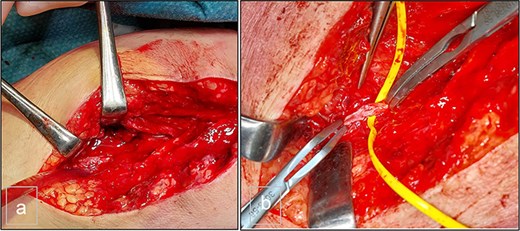

The Doppler ultrasonography was supplemented with contrast-enhanced computed tomography (CT angiography) and 3D reconstructions. The CT scan identified a hematoma with a pseudoaneurysm located at the inferior aspect, measuring 28 mm in height, 29 mm in the transverse axis, and 20 mm in the anteroposterior axis. The lesion was supplied by the PTA, which flowed laterally to the pseudoaneurysm. The medial wall of the PTA appeared discontinuous over a length of ~6 mm (Fig. 2).

Computed tomography. (a) Lateral view, (b) posterior view, and (c) vascular reconstruction. The medial wall of the posterior tibial artery appeared discontinuous over a length of ~6 mm.